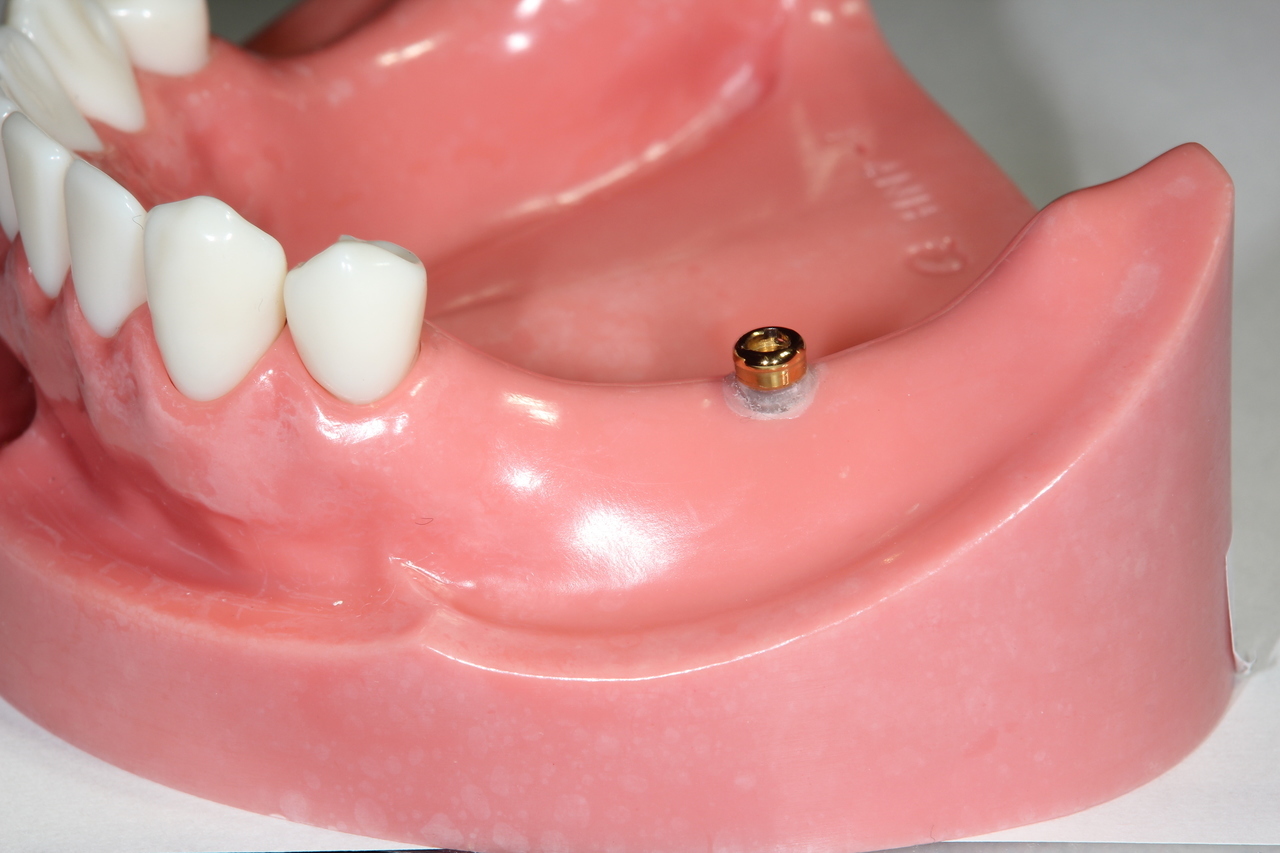

欠損部分に1本のインプラントを埋めます。

インプラントに凹の装置、入れ歯に凸の措置を装着し接続することで入れ歯のかたつきを解消し、しっかり噛むことができます。

着脱式の入れ歯です。お手入れは外して洗浄します